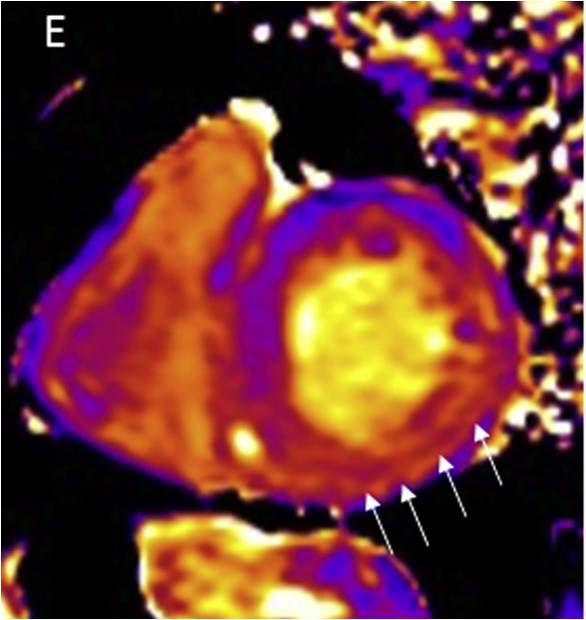

CA左室整体收缩期纵向峰值应变,基部收缩受损,心尖部接近正常(apical sparing)

(Circ Res. 2017;121:819-837)

心肌结节病 ECHO:A 前间隔变薄; B 下壁基部瘤样扩张;C 肺动脉高压,右室大 ; D 左室整体收缩期纵向峰值应变(室间隔及心尖部重度减低,其他部位轻度减低)

(CircRes.2017;121:819-837)

18F-FDG PET:左室侧壁基部摄取